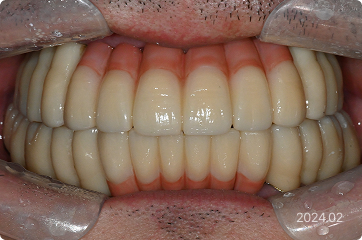

57세, 남 ㅣ전체 임플란트

“치아가 거의 없어서 식사가 어렵고, 일상생활이 제대로 안 돼요.”

치료 전

원데이 임플란트

치료 후

• 대부분의 치아 상실, 식사 및 생활 불가능

• 하루만에 전체 임플란트 식립

3일만에 전체 즉시 기능 예비치아 장착

• 6개월 후 최종 보철까지 완성